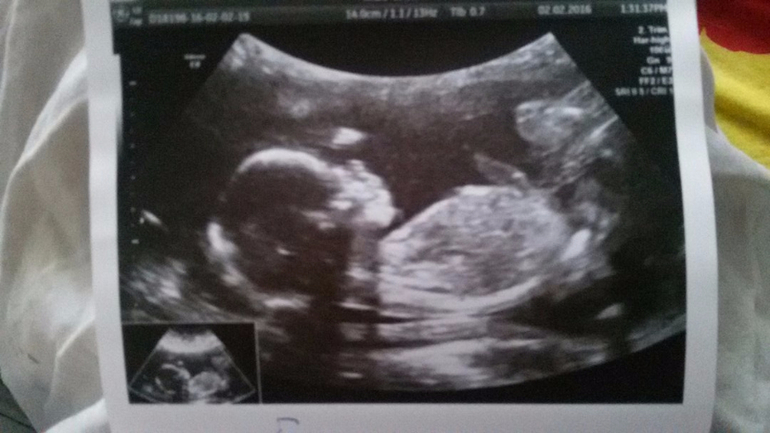

Малышки крутились все исследование сфотать смогли хорошо лишь младшую, старшая показала фигу и повернулась спиной ( муж ржал и умилялся одновременно)

Срок нам уменьшили, если по первому скринингу сегодня 18,4 нед то по сегодняшнему ровно 18 у старшей и 17,6 у младшей. Развиваются равно, младшая конечно помельче, но потолще, как раз что-то жевала на узи:)

И так представляю вам: Климовских Лилит и Ливия Дмитриевны :